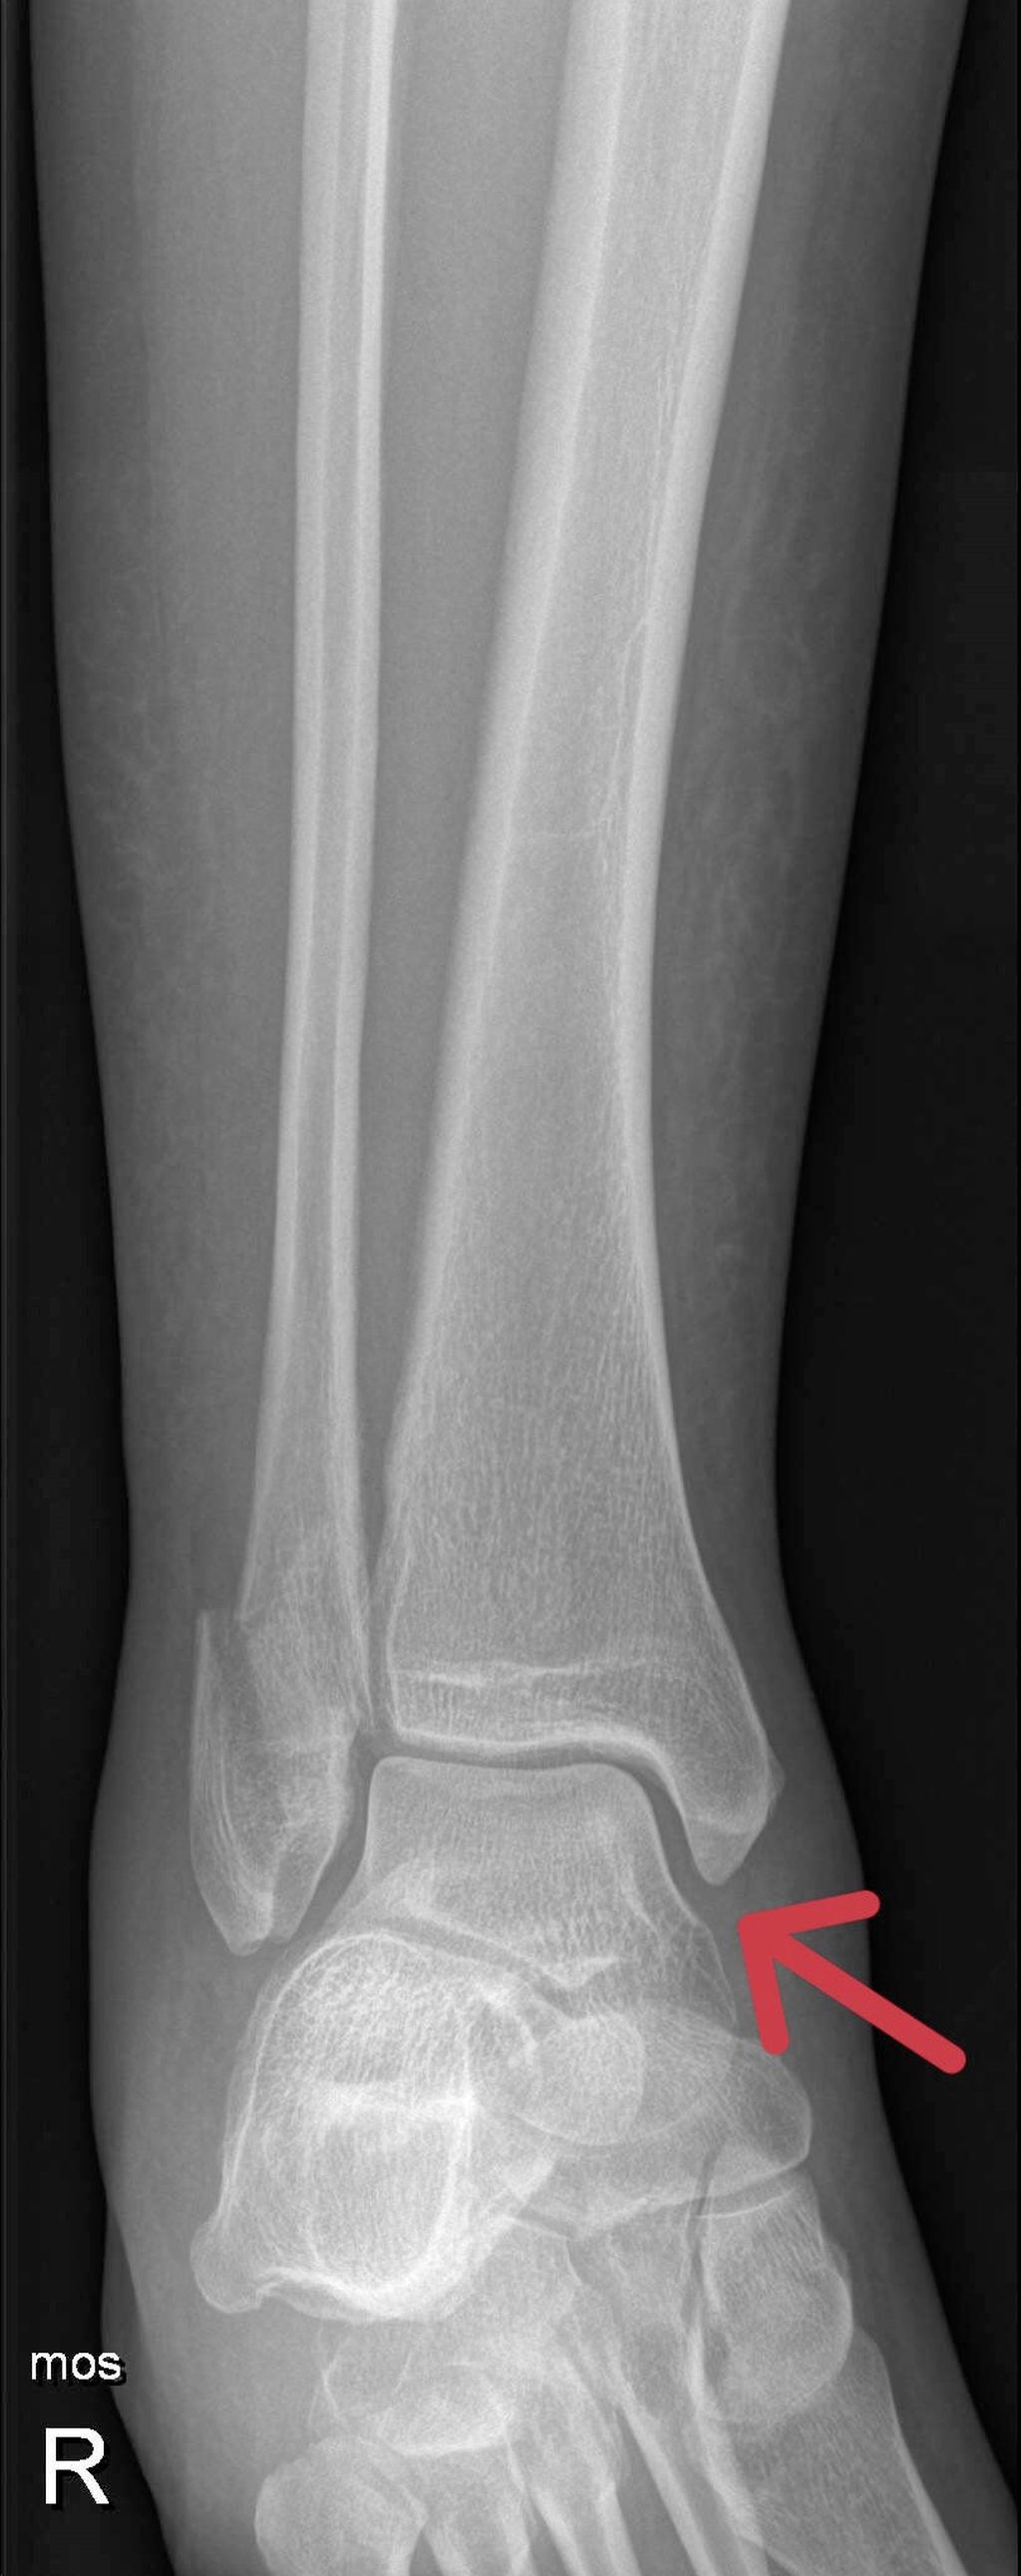

Als Standarddiagnostik erfolgt eine Röntgenaufnahme des Sprunggelenkes in zwei Ebenen. Die a.p-Aufnahme wird in 15–20° Innenrotation des Unterschenkels (Mortise-View) durchgeführt. Zur Beurteilung der Integrität des Deltabandes ist der Abstand zwischen Sprungbein und der lateralen Kortikalis des Innenknöchels („medial clear space“, MCS), entscheidend. Bei Werten <4mm ist das Deltaband intakt und die Fraktur stabil. Ist der MCS größer als 4mm oder gibt es klinische Zeichen einer Deltabandverletzung, muss weitere Diagnostik zur Feststellung der Stabilität durchgeführt werden.

Eine weitere Möglichkeit ist die Röntgenaufnahme im Stehen unter Vollbelastung nach 5–10 Tagen. Zeigt sich hierbei ein unauffälliger MCS, werden in der Literatur gute klinische Ergebnisse bei konservativer Behandlung beschrieben. Dawe et. al stellten fest, dass der „Gravity-Stresstest“ bei Außenknöchelfrakturen signifikant häufiger positiv ausfällt als der Röntgenbelastungstest (45% vs. 3,7%). Dementsprechend höher war die Anzahl der operierten Patienten und der damit verbundenen Komplikationen. In der Studie von Holmes et. al wurden bei 51 Patienten mit einem MCS <7mm (∅ 4,42mm) im „Gravity-Stresstest“ normale Werte in der Röntgenuntersuchung in Vollbelastung beobachtet. Diese Patienten wurden konservativ behandelt und zeigten gute klinische und radiologische Resultate. 90–98% der isolierten Außenknöchelfrakturen können trotz positiver „Stresstests“ oder klinischer Zeichen einer Instabilität bei negativem Röntgenbelastungstest konservativ mit gutem Outcome behandelt werden.